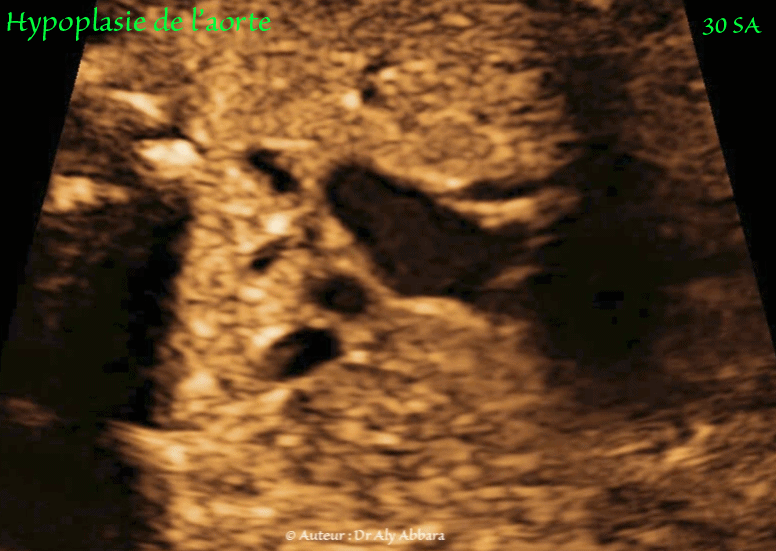

• Images échographiques montrant des multiples signes échographiques liés à la présence d'une hypoplasie de l'aorte dans sa portion ascendante et horizontale.

Coupe haute des trois vaisseaux et trachée montrant :

• Hypoplasie de l'aorte ascendante et de crosse de l'aorte : elle est visible sur la coupe des trois vaisseaux et de la trachée :

• le diamètre de l'aorte ascendant = 3,4 mm ;

• le diamètre de l'aorte horizontale = 2,5 mm ;

• à titre de comparaison, le diamètre du tronc pulmonaire = 8,5 mm.